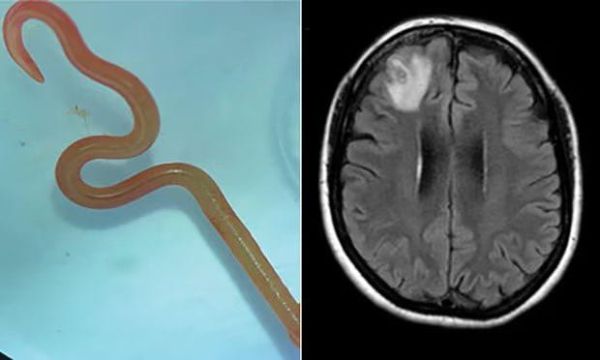

אישה אוסטרלית שהגיעה לבית החולים והתלוננה על כאבי ראש חריפים גילתה כי תולעת טפילית נדירה התחפרה במוחה, המקרה נחשב לראשון בעולם של הדבקה כזו